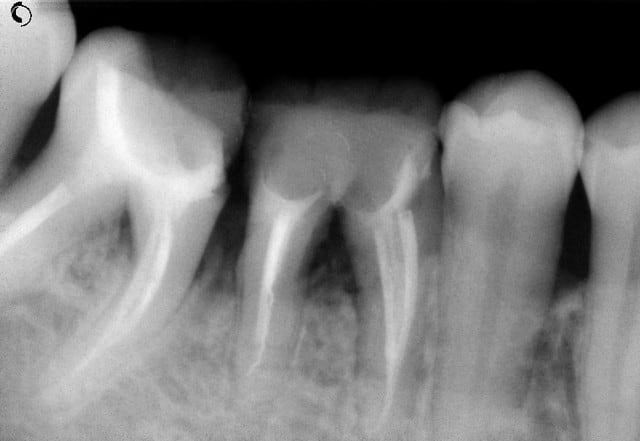

Ceci est un exemple de traitement de poches par photo-ablation en une seule séance en mode continu sans contact, cette technique diffère des traitements par lasers fibrés.

Après sondage et traitement médical, la gencive non attachée est volatilisée avec stérilisation et hémostase immédiate. La cicatrisation est rapide et la ré-attache se réalise en quelques jours, laissant dégagés les espaces biologiques afin de permettre un entretien aisé par le patient, la texture de la gencive prenant un aspect en peau d'orange et reformant progressivement un feston.